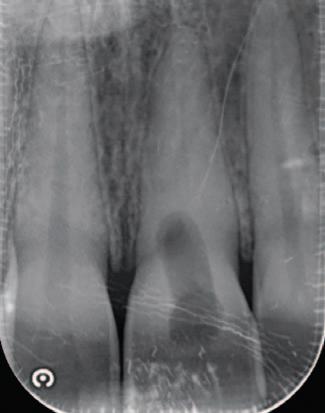

A 30-year-old patient presented to your clinic complaining of a discoloured front tooth (Figures 1 and 2). There was no pain or other symptoms associated with it and it has become increasingly discoloured over time.

1. What is the likely reason for this type of discolouration?

2. What special tests do you perform as part of your exam?

3. What are the potential sequalae for this tooth?

4. What are the possible treatment options for

this tooth and what are the potential difficulties with doing a root canal treatment?

Answers on page 45.

FIGURE 1: Patient presenting with discoloured front tooth. FIGURE 2: Periapical radiograph 1.